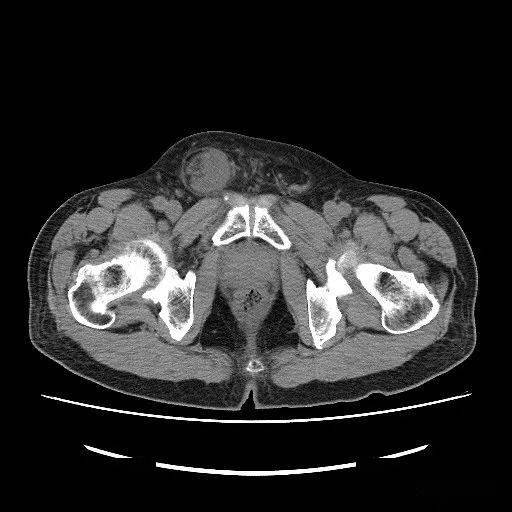

76岁女性,左侧腹股沟区可复性包块20年,不能还纳伴疼痛3天.